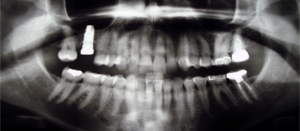

Your first visit to the doctor typically includes an x-ray that allows the

doctor to view the structure of the jaw, the position of any teeth that have

not yet erupted, malformed roots, and tooth decay.